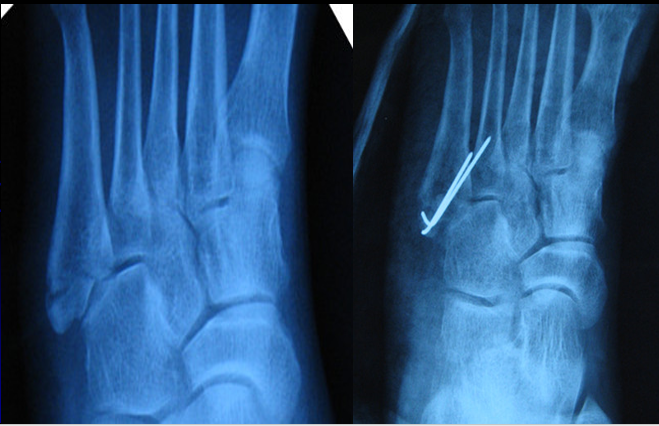

经皮空心钉固定适合于骨折块较大,移位较少,骨质好的患者。具有微创损伤小、不干扰局部的血运、固定牢靠、恢复快等优点。

操作要点:操作要在透视监视下进行,且导针一定要从尖端打入,且在第四、五跖骨间连接以远穿出对侧骨皮质,这样生物力学强度最佳。

实心螺钉髓内固定——新的选择避免空心螺钉固定本身的不足:插入导针断裂、反复插入导针削弱皮质骨和松质骨、空心螺钉固定强度不足。

07骨折不愈合

1.骨折不愈合的原因

• 重视不足,尤其是Jones 骨折;

• 石膏、矫形支具、弹力绷带等外固定方法固定不牢;

• 由于解剖特点,近端血运较差,同时基底部是多种肌腱、韧带的附着点,容易再移位,导致骨折的延迟愈合和不愈合。

2.骨折不愈合的处理如骨折超过2个月,因断端分离及骨吸收而出现不愈合,因其骨质发生废用性疏松及断端骨缺损的因素,应使用锁定接骨板螺钉以达到坚强固定的目的,同时应根据情况进行断端植骨以促进骨折愈合。